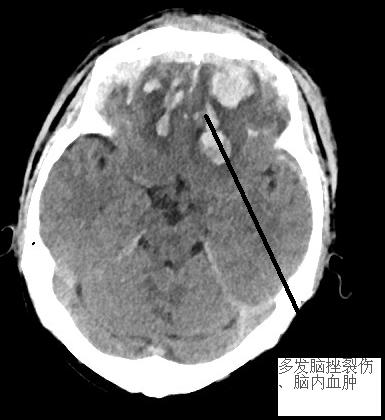

患者黃先生,在家中上衛(wèi)生間時不慎摔倒,受傷后出現(xiàn)昏睡情況,一開始家屬以為是小事,并沒有上心。后來,發(fā)現(xiàn)黃先生持續(xù)昏睡,怎么叫都沒有應答,且偶有躁動現(xiàn)象,并出現(xiàn)大小便失禁、發(fā)熱等情況,意識到病情嚴重,立即送至我院。經(jīng)急診CT檢查,提示黃先生雙側(cè)額顳葉多發(fā)腦挫裂傷伴腦內(nèi)血腫,額部硬膜外血腫,額部、左顳部及大腦鐮前部硬膜下血腫,創(chuàng)傷性蛛網(wǎng)膜下腔出血,額骨骨折,出血量較大,雙側(cè)額顳葉多發(fā)腦挫裂傷伴腦內(nèi)血腫臨近腦干(生命中樞),環(huán)池部分變窄,若病情再繼續(xù)惡化,將造成腦干功能受損,甚至影響呼吸、心跳,符合開顱手術指征。在征得家屬知情同意后,神經(jīng)外科團隊立即與前來本院查房的福醫(yī)大附二院黃金鐘主任就黃先生病情進行深入研討,制定手術方案,同時完善術前各項準備工作后,立即進入手術室緊急開顱手術。手術過程中,予以清除血腫,腦組織壓力減低,腦血管搏動有力。術后復查CT,手術區(qū)域血腫基本清除,環(huán)池受壓緩解,患者生命征平穩(wěn)。隨后進行后續(xù)康復治療。